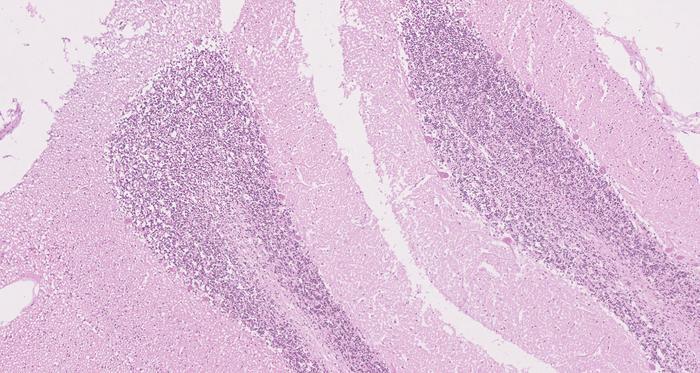

Recent advancements in genetic research have shed light on the perplexities surrounding the development of tumors in individuals with neurofibromatosis type 1 (NF-1), a genetic disorder characterized by the growth of tumors called neurofibromas and the presence of distinctive skin markings. While earlier theories predominantly attributed tumor formation to genetic changes alone, new findings from researchers affiliated with the Wellcome Sanger Institute, among others, suggest that these genetic alterations can also be present in normal tissues. This paradigm shift emphasizes the role of additional factors contributing to tumor development beyond mere genetic predisposition.

In the comprehensive study published in the journal Nature Genetics, a team of scientists meticulously examined genetic samples from children diagnosed with NF-1. Through their innovative approach, the researchers analyzed nearly 500 separate tissue samples, comparing them with those from children without the condition. Astonishingly, they discovered that the same genetic changes leading to loss of function of the NF1 gene were prevalent in normal tissue samples, not just in tumor cells. This revelation challenges long-held beliefs about the causative mechanisms of NF-1 and suggests a need for a more nuanced understanding of its pathogenesis.

Moreover, the team’s investigations uncovered a distinct pattern of genetic alterations localized in tissues of the nervous system—this particularity correlates with the known predisposition for tumors to arise in these areas among individuals with NF-1. Consequently, understanding these specific genetic motifs could aid clinicians in tailoring monitoring programs and identifying patients who may be at elevated risk for developing tumors. The findings underscore that additional biological factors, including cellular context and anatomical specificity, might dictate the likelihood of tumor formation in genetically susceptible individuals.

Image Credits: Credit: Thomas Oliver / Wellcome Sanger Institute